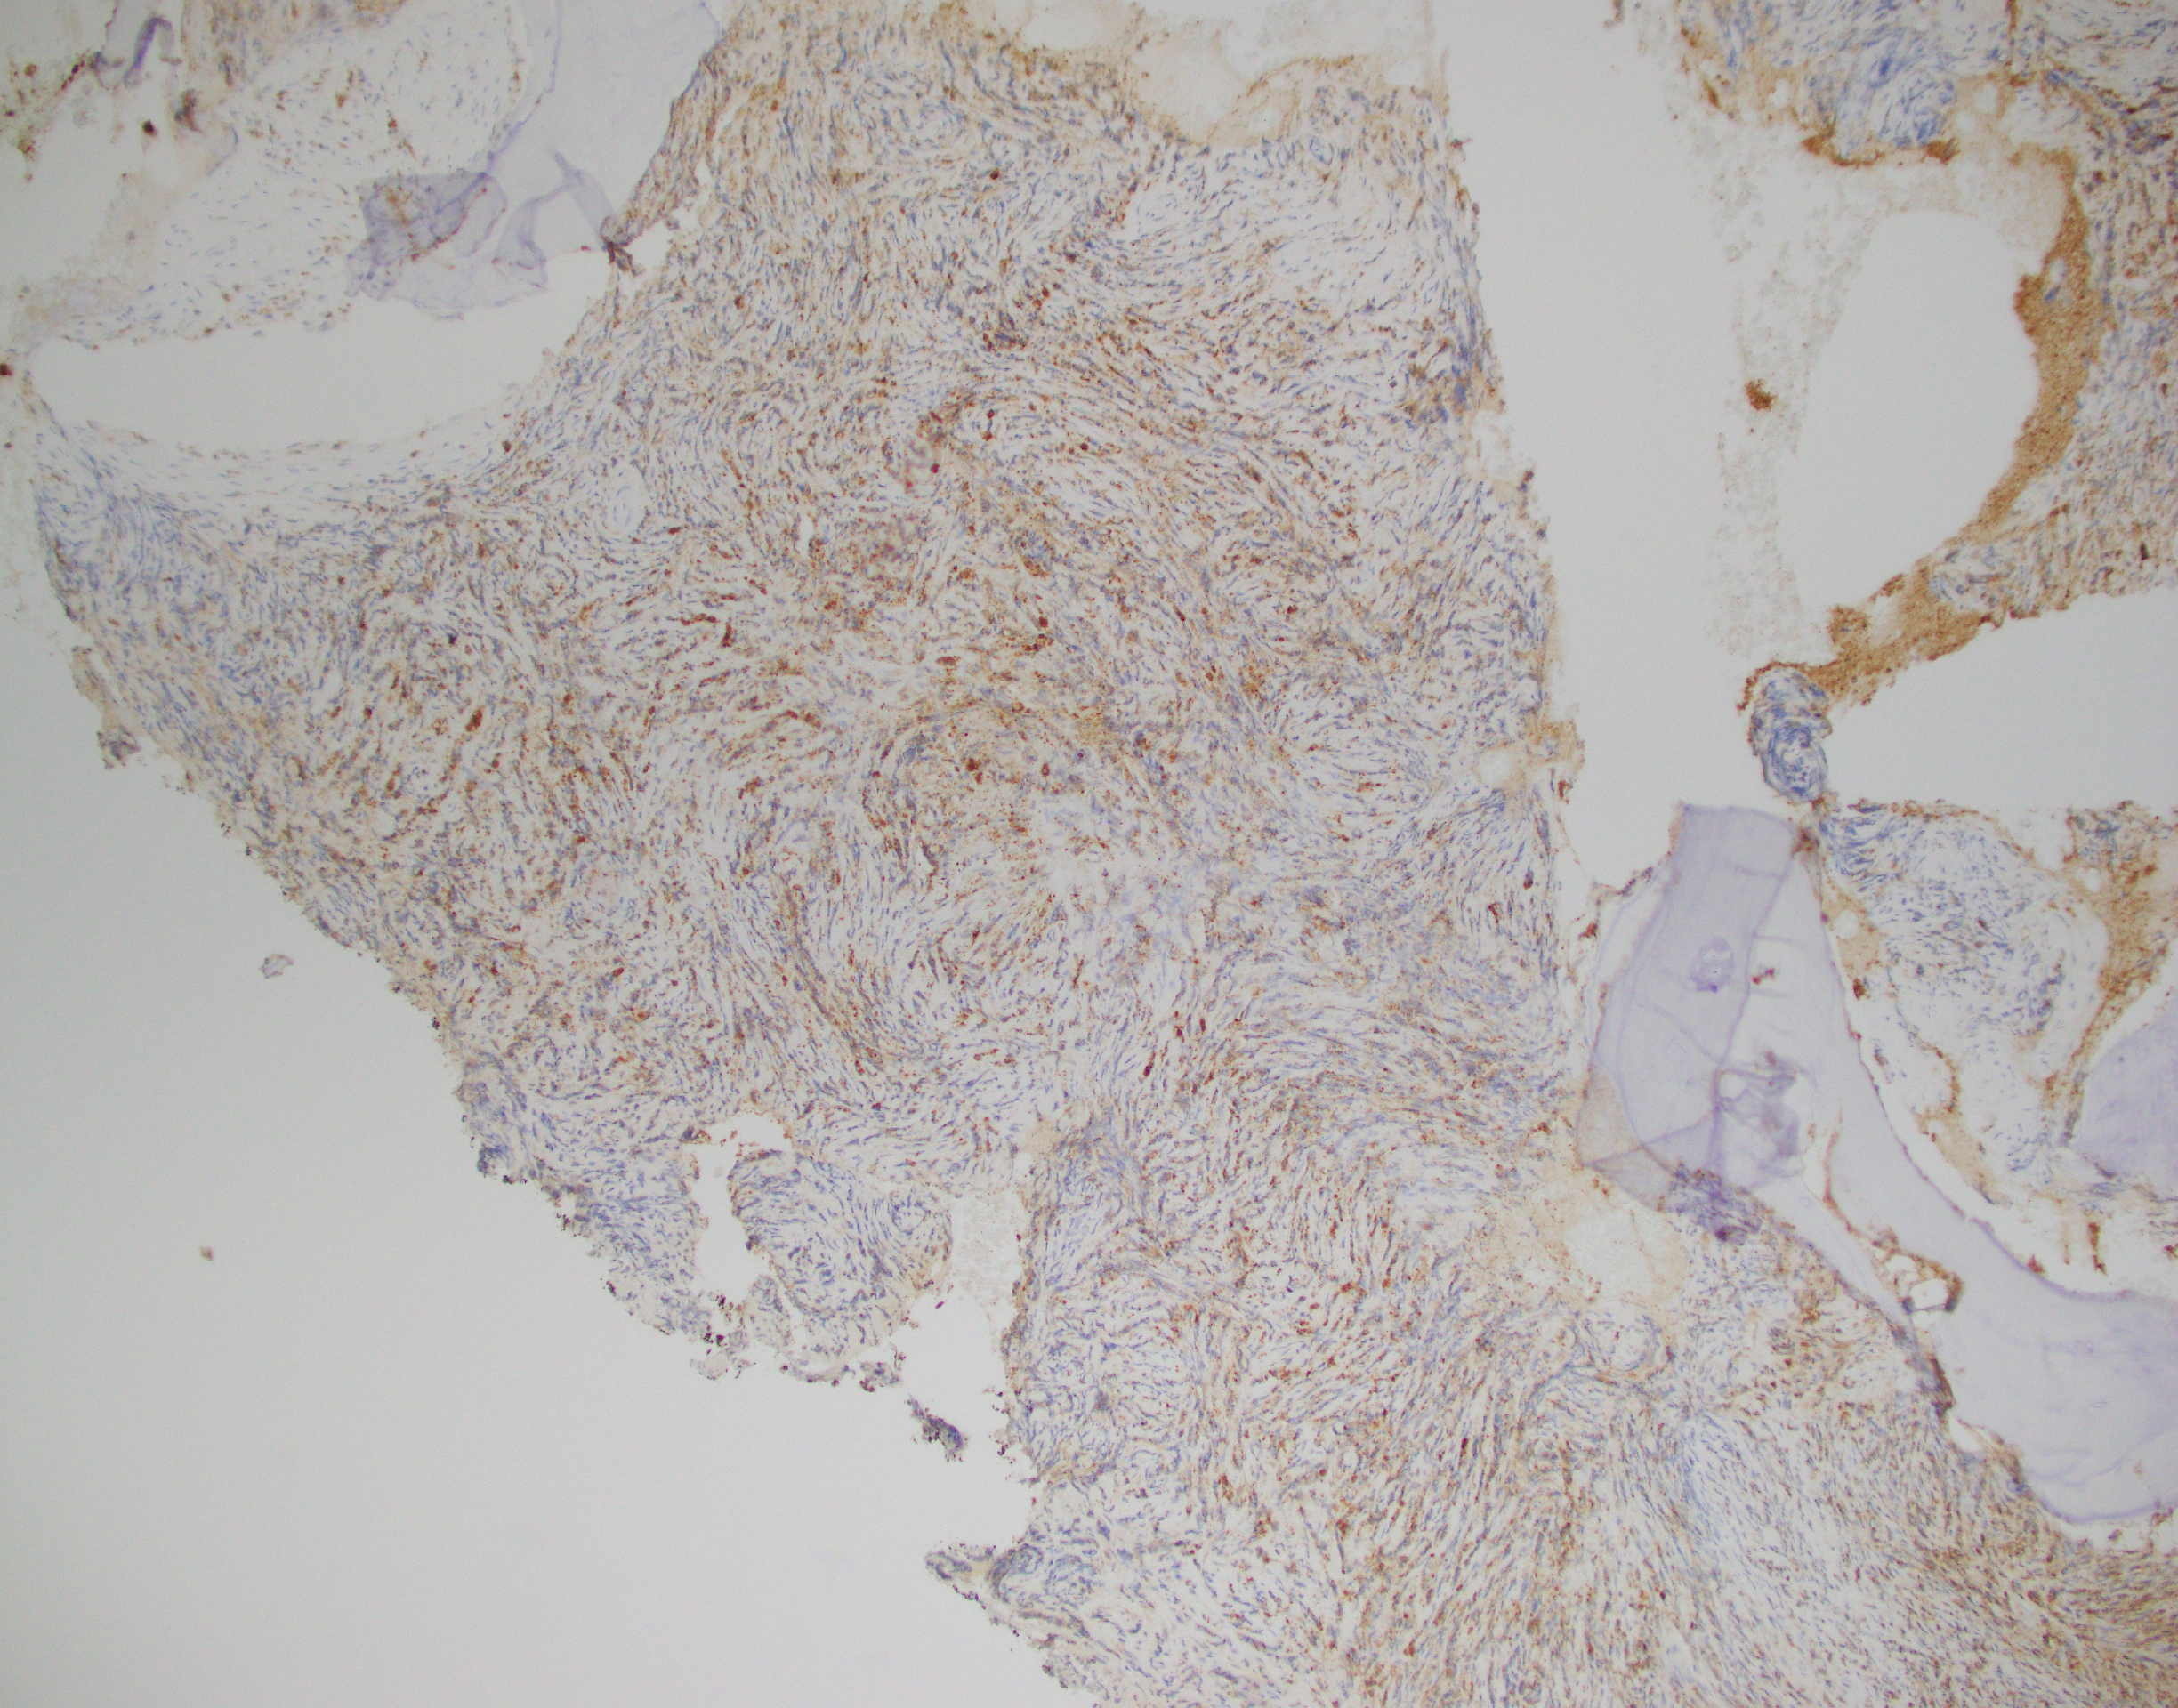

Essentially, this patient was found to have Li-Fraumeni after the second manifestation of an acute sarcoma—the first being osteosarcoma in her teenage years and the second breast cancer in her 30s. Both cancer diagnoses were treated accordingly, and this patient was going through routine work-up for anemia before being referred to the Mayo Clinic. By the time the patient reached there, the clinical investigation included a battery of testing for causes of anemia—all within normal limits—so a bone marrow examination was performed which revealed a significant, though not acute (<20% blasts), myelodysplastic process. A follow-up in-house bone marrow collection revealed hypercellular marrow, now in acute myeloid proliferation, with abnormal myeloid cell maturation and very complex cytogenetics. She had a very complex karyotype and several detectable mutations which were consistent with the WHO’s classification and description of therapy-related myeloid neoplasm as a sequale to the treatments she received for her prior cancers. In the setting of a patient with LFS, it is almost impossible to avoid malignancy. The following slides are a (very abridged) summary taken from my presentation of this patient’s case:

In a case report from 2017 I discussed a patient who had bilateral lung nodules several years after being treated for breast carcinoma. It was initially thought to be relapse but was later correctly diagnosed as de novo peripheral T-cell lymphoma (PTCL). This could have very well been the same clinical scenario, with a different cell lineage. The lesson gleaned here is the same as those ASH/CAP guidelines: stay organized, consistent, and purposeful with your testing and investigation. What came down to a few immunohistochemical markers in this PTCL case could make all the difference in another case. Missing the clinical history and specific genetic mutations present in this LFS/AML patient could have led to a diagnosis of a myelodysplasia related AML instead of a therapy-related one, especially in the setting of such a severe germline pre-disposition.